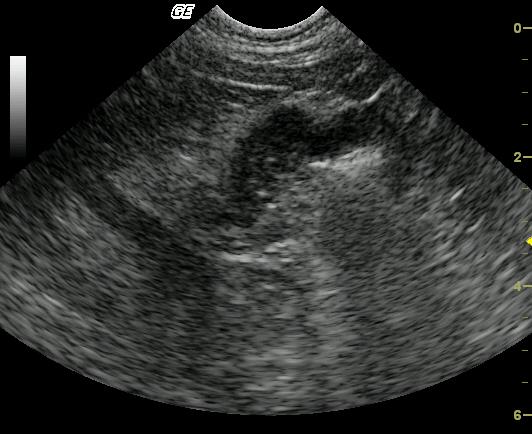

The transverse image of the stomach reveals marked focal thickening of the gastric wall extending from the ventral surface to the lesser curvature. The affected gastric wall is hypoechoic and lacks wall layering. The echogenic wedge-shaped foci noted in the near field within the thickened gastric wall may represent an area of necrosis or fibrosis. Video: Loss of detail is noted in the affected pyloric outflow tract meeting neoplastic criteria but complicated inflammatory disease may present occasionally in this manner. The lesion is focal and may be resectable.

Gastric wall mass consistent with neoplasia such as lymphosarcoma or a similar round cell tumor. Severe, focal inflammatory or granulomatous disease is considered less likely.